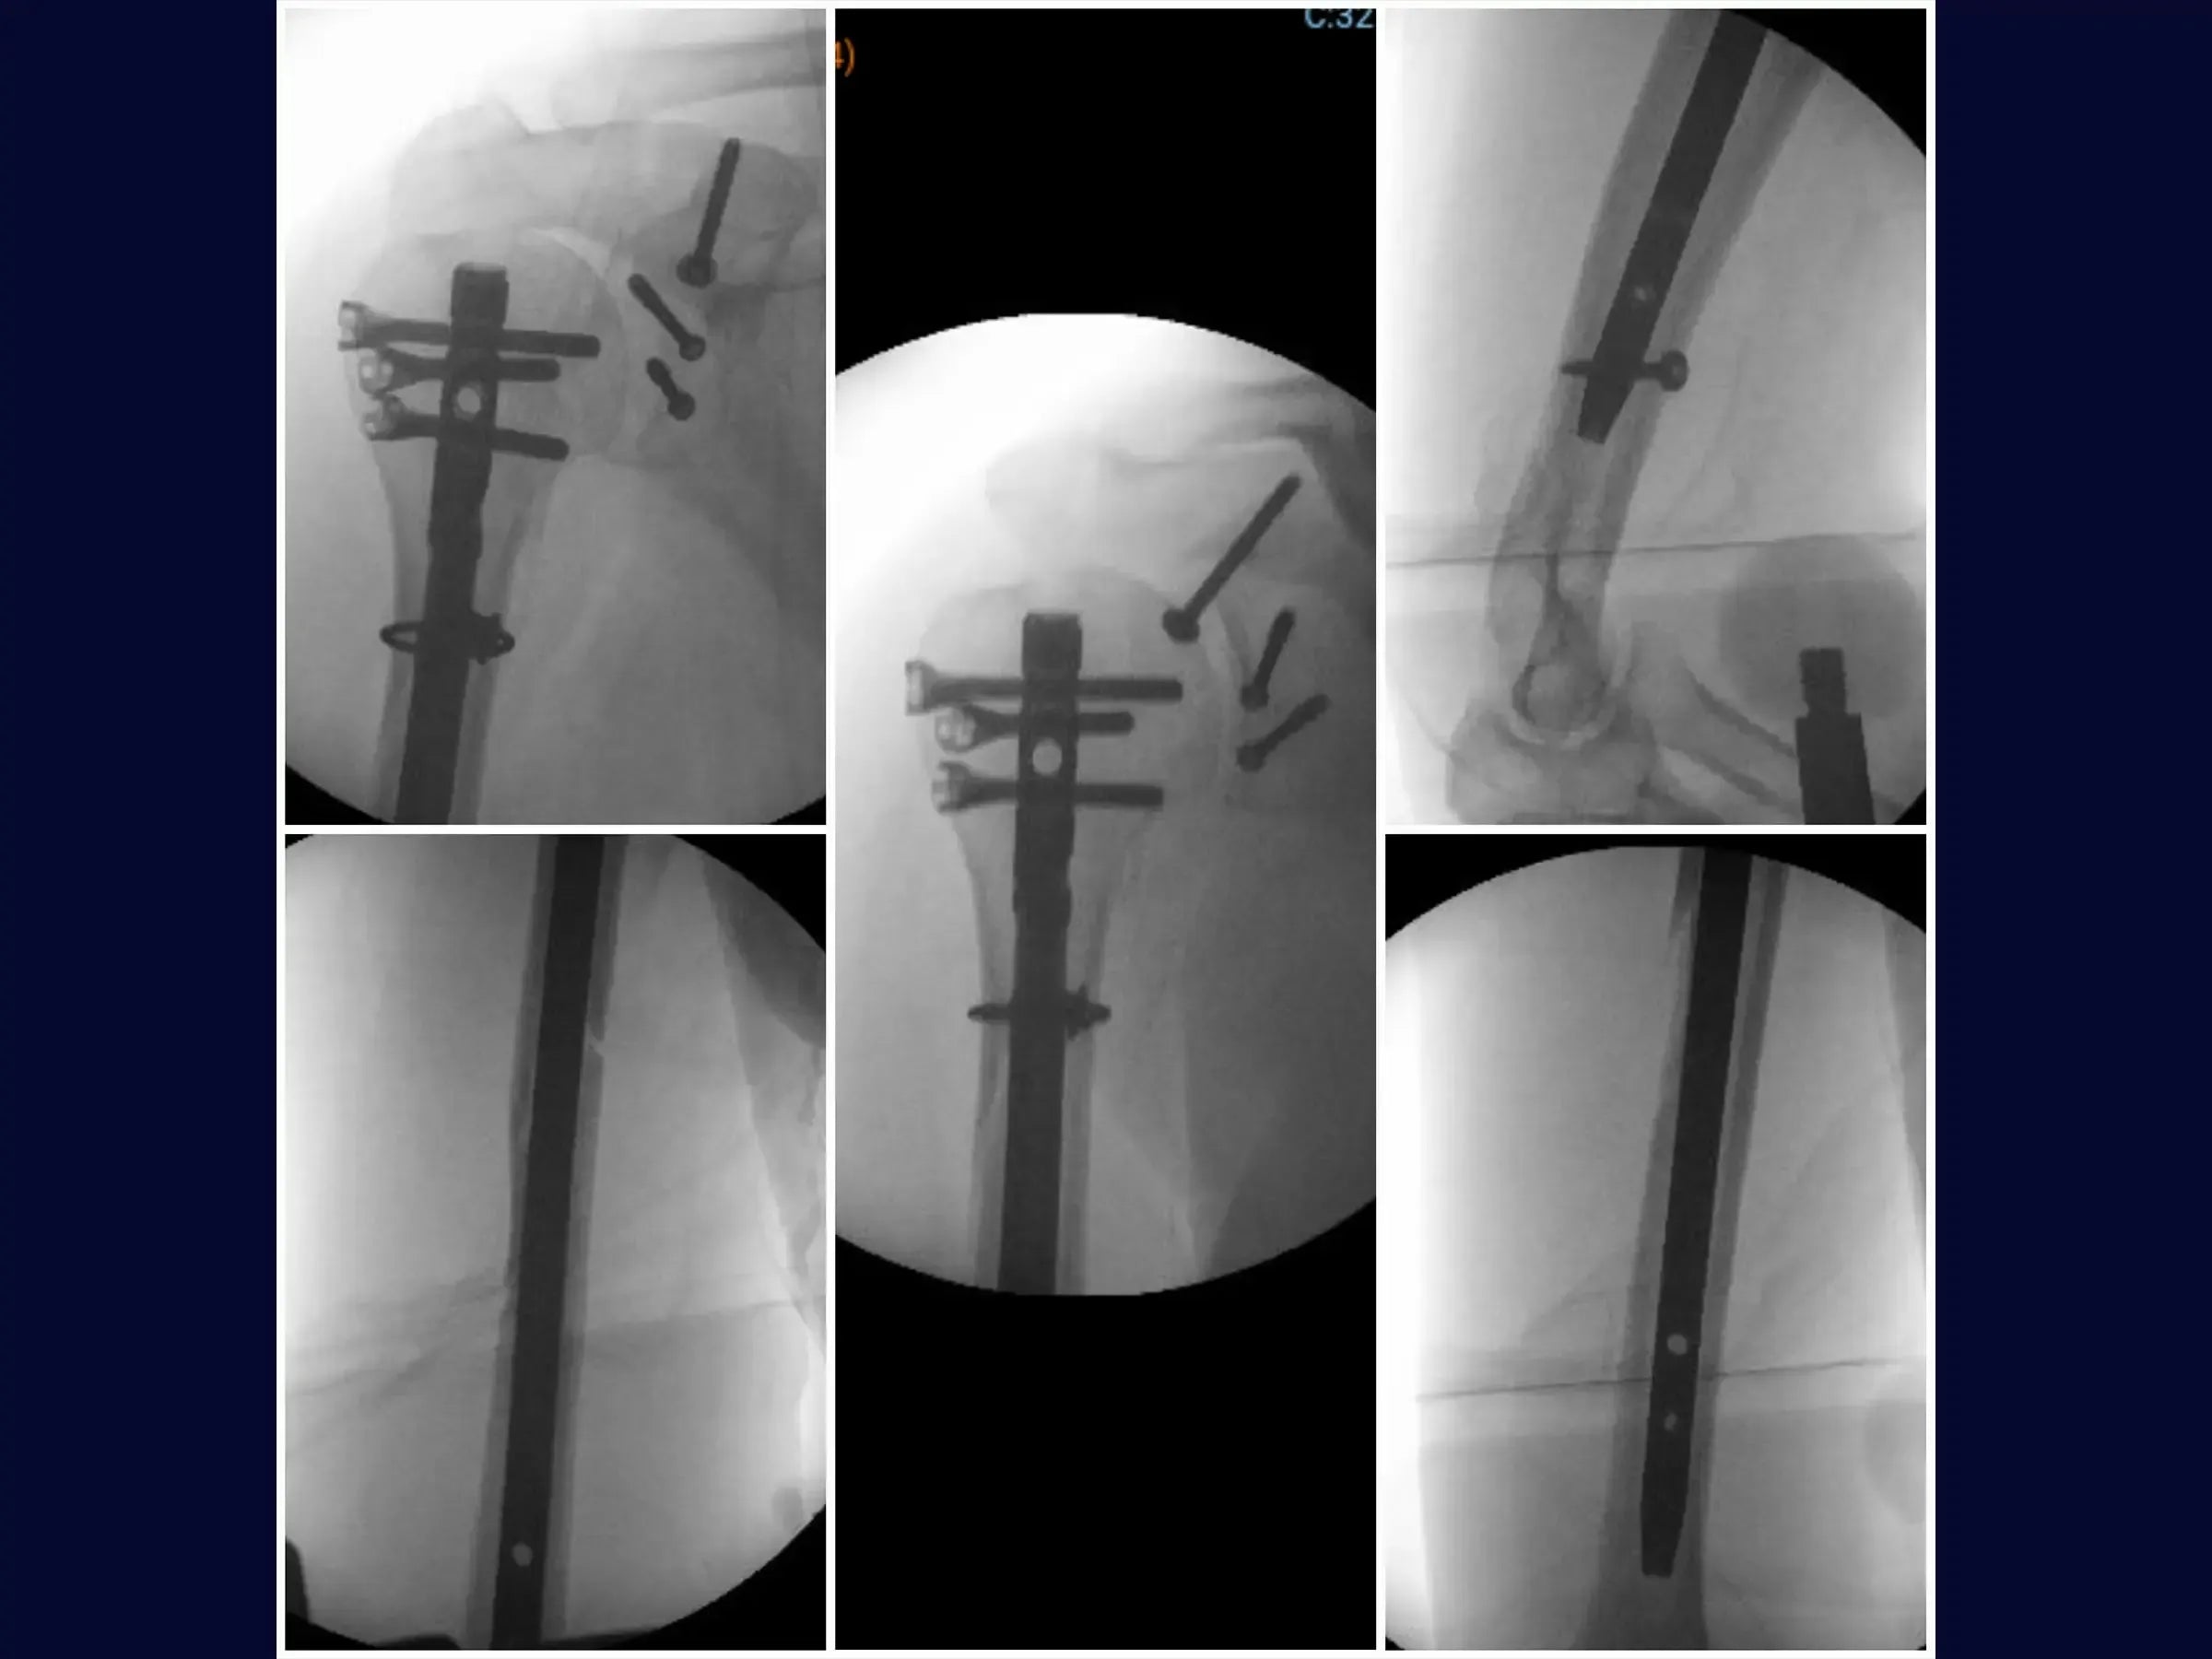

- Osteosíntesis de fracturas glenoideas con tornillos de compresión.

- Posicionamiento estratégico de retractores: protocolos para posicionar retractores en el borde posterior de la glenoides y entre el subescapular/cápsula para maximizar el campo operatorio.

- Osteosíntesis efectiva: demostración de visualización transversal del fragmento y técnica de fijación con tornillos de compresión para la estabilidad de la fractura glenoidea.